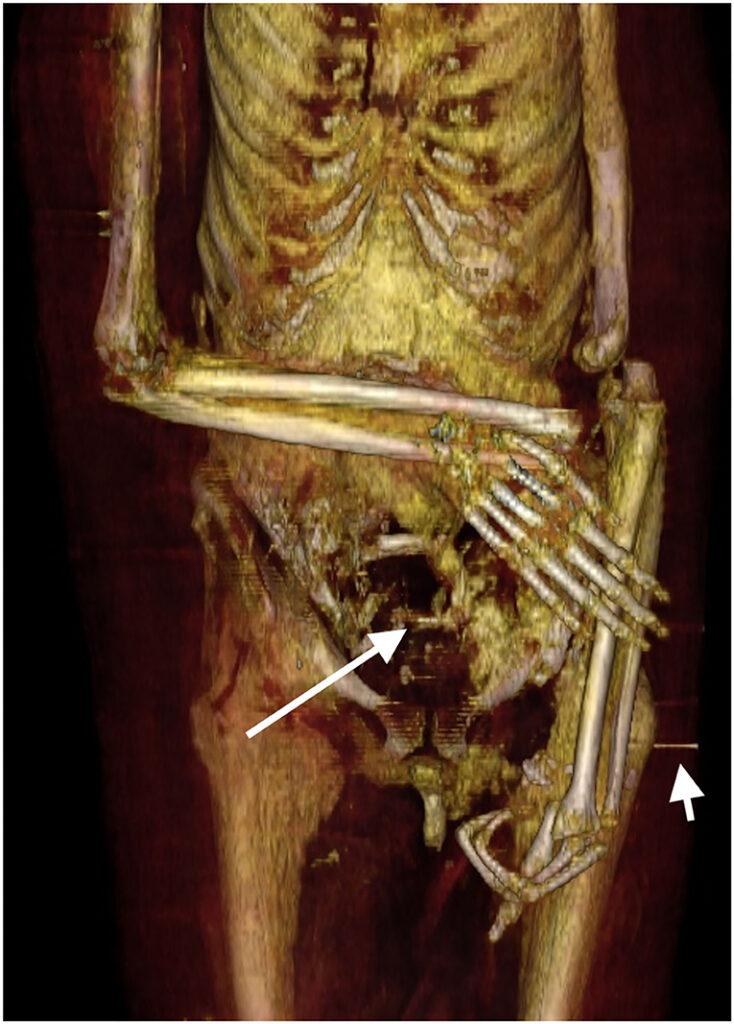

La evidencia de ladrones de tumbas también estaba presente. El brazo izquierdo fue desarticulado y luego vuelto a envolver extendido junto al cuerpo de la momia. El brazo derecho de la momia, sin embargo, está doblado por el codo con el antebrazo superpuesto al abdomen, lo que indica que probablemente ambos brazos alguna vez estuvieron cruzados de la misma manera. Dos dedos de la mano izquierda también fueron desmembrados, probablemente por ladrones de tumbas, y fueron localizados dentro de un gran defecto de la pared de la cavidad abdominal. Más notable aún, el cuello de la momia había sido cortado, la cabeza decapitada y se volvió a unir con una banda de lino tratada con resina con un amuleto colocado debajo.